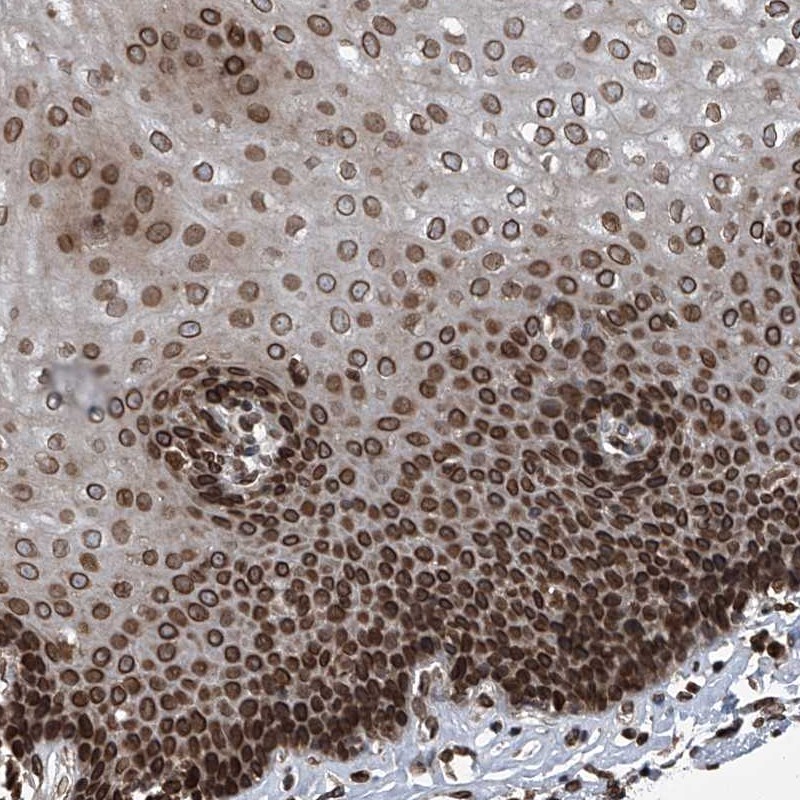

Immunohistochemical staining of human esophagus shows strong nuclear membranous positivity in squamous epithelial cells.